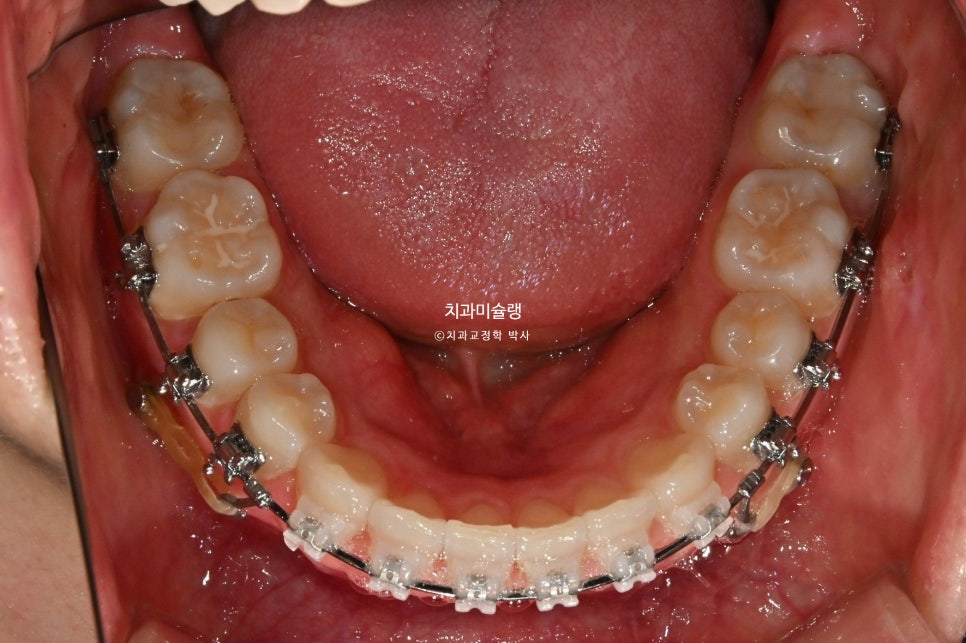

2026년 1월 – 치료 시작 1년차

치료 시작 1년차 모습입니다. 치료 도중 턱관절 불편감은 딱히 없었습니다. 인비절라인에서 클리피씨로 바꿨기 때문에 턱관절이 편해진건 아닙니다. 앞니 과개교합으로 인한 조기접촉을 초기에 먼저 해결했기 때문이죠. 고정용 나사를 4군데 심고 전체치열을 뒤로 당기고 있습니다.

중심선은 정확히 맞으며 과개교합은 개선되었습니다. 브라켓 주변부 양치가 안되어 안타깝게도 충치가 좀 생겼습니다. 어금니 교합관계는 1급관계를 달성.